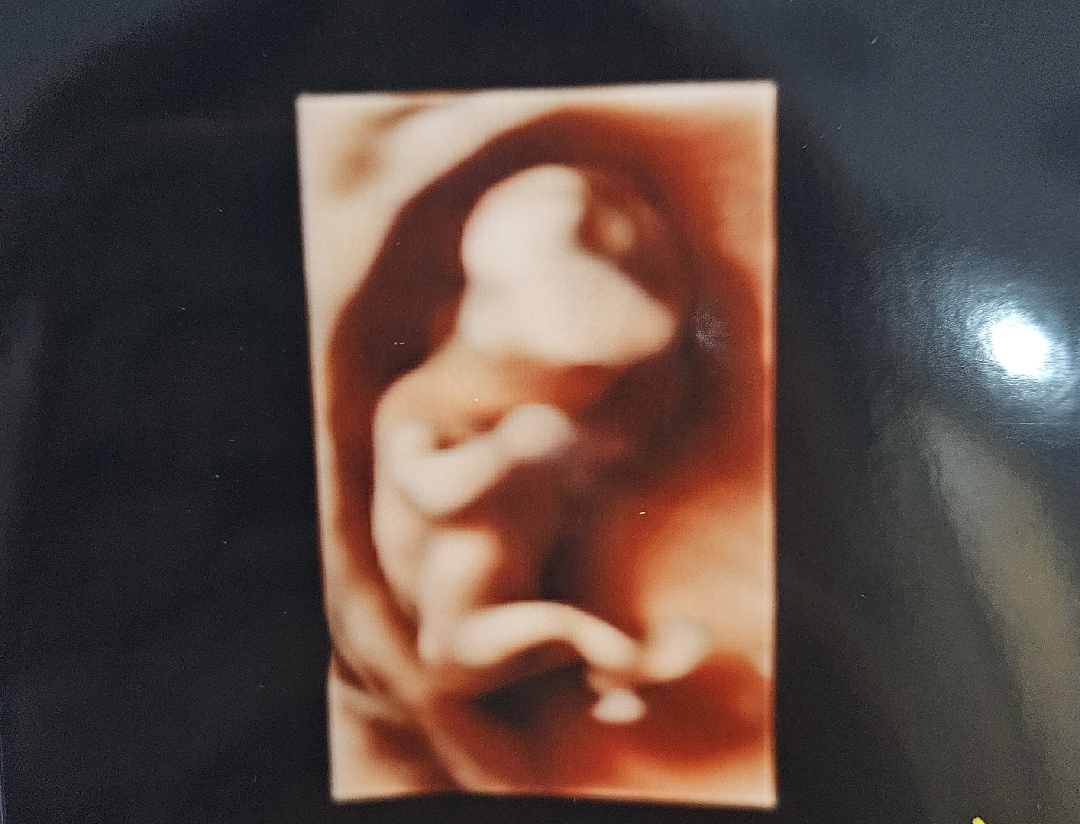

13주2일, 성별 알 수 있을까용?

알수없는 두드러기로 4갤째 고생중이라 참다참다 낼 교수님께 여쭤볼건데, 여기 병원은 항상 입체초음파 봐주시거든요 ! ! 13주 2일에 성별 알 수 있을까요?!?!? 요 사진은 기형아검사 1차 때 다리꼬고 있는 아가에용

13주2일이였어요!ㅋㅋㅋ 성별궁금해서 니프티까지했는데 왜했을까싶게 빨리 보여줬어요..ㅎㅎ